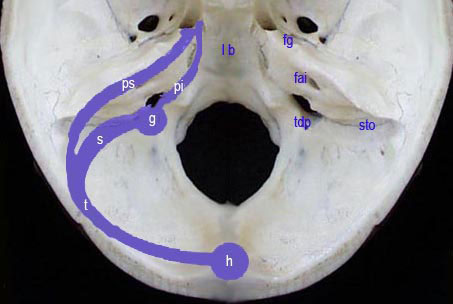

Le cervelet est situ dans la fosse postrieure, loge osto-fibreuse inextensible, limite :

Outre le cervelet, cette loge est occupe par le segment bulbo-protubrantiel du tronc crbral & par les deux espaces ou angles ponto-crbelleux quÕils dlimitent entre eux.

LÕangle ponto-crbelleux est un espace paramdian exigu & profond, dlimit de chaque ct par la protubrance reprsente principalement par le PCM, la partie rostrale de la face latrale du bulbe, & par la face ventrale de lÕhmisphre crbelleux.

Sch.31 Š Aspect ventral

Il est occup par le prolongement latral de la citerne pontique, par le flocculus qui masque le plexus chorode latral du 4” ventricule, par de nombreux nerfs & par des vaisseaux crbelleux. CÕest ce niveau que se dveloppent les tumeurs de la VIII” paire

Les troncs nerveux ont une disposition cardinale : trs en dedans le VI, en haut le trijumeau, en dehors le faisceau acoustico-facial dirig vers le pore auditif interne, &

en bas le groupe des nerfs mixtes (IX-X-XI) orients vers le trou dchir postrieur.

LÕaspect endocrnien de cette de la loge crbelleuse met en vidence les repres suivants:

Sch.32

l p : lame basilaire

f g : fossette du gg. de Gasser

fai : foramen auditif interne

tdp : trou dchir postrieur

sto : suture temporo-occipitale

ps : sinus ptreux suprieur

pi : sinus ptreux infrieur

g : fossette du golfe de la jugulaire

s : sinus sigmode

t : sinus transverse

h : pressoir dÕHrophile (Torcular)